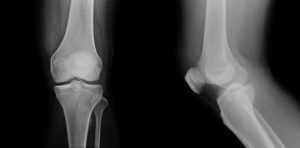

Teknolojinin tıp alanındaki ilerlemeleri, ortopedik uygulamalarında da dönüşüme yol açmıştır. Bu dönüşümlerden biri de robotik sistemlerin diz protezi cerrahisinde kullanılmasıdır. Robotik diz protezi cerrahisi, ileri teknolojiyle donatılmış sistemlerdir. Teknolojinin kullanımıyla, diz ekleminin işlevselliğini yeniden kazandırmayı hedefler.

Kullanıldığı bölge ve hassas bir şekilde protez yerleştirmesine yardımcı olduğu bir prosedürdür. Bu sistem, üç boyutlu görüntü, hassas hareket kontrolü ve gerçek zamanlı geri bildirim gibi özellikler sunar. Böylece ameliyatın başarısını artırır. Diz ekleminin doğru hizalanmasını, uygun yerleştirilmesini sağlar. Ayrıca optimal implant pozisyonunu da sağlayabilir.